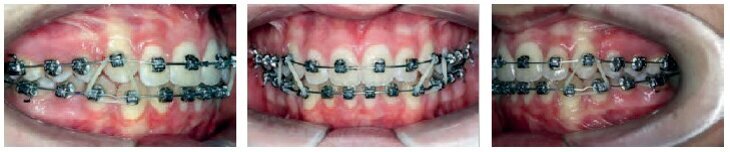

VISIT NO 1

Both appliances bonded on the same day.

SAP bracket placement

Torque Selection

Maxilla: Super low torque on the incisors – super torque on the canines.

Mandible: Low torque on the incisors – super torque on the canines.

014 CN archwires were placed along both arches, from the 1st molar to the 1st molar, without stops.

Bite turbos were bonded to 13 – 23 in order to unlock the occlusion, promote leveling, and protect the brackets on the lower arch.

VISIT NO 2: 4 MONTHS

The patient returned 4 months later. The arches showed excellent initial progress in terms of leveling.

New 014 archwires were placed to continue the leveling-alignment process.

Anterior stops were placed on both arches.

VISIT NO 3: 10 MONTHS

Ten months into the treatment, the 014 archwires were kept on, and both arches showed excellent progress in terms of leveling-alignment. Crowding was fully resolved.

A panorex was done to confirm the proper placement of the initial brackets.

Only the maxillary central incisors (whose roots showed significant proclination) were rebonded with standard torque brackets.

Both arches were fitted with 16x25 CN archwires, and the bite turbos were gradually reduced.

VISIT NO 4: 14 MONTHS

It was as if time was doing the work for us. After just 2 visits over 14 months, a remarkable correction was observed in all 3 orders.

Nonetheless, 13 was repositioned to provide a more gingival placement and to correct tipping (see the panorex taken 4 months earlier, which shows an excessive tip-back of this tooth).

For the maxillary arch, the 16x25 CN archwire was replaced with an 18x25 CN archwire, and the mandibular arch was fitted with a 17x25 TMA archwire. The patient was also required to wear vertical intercuspation elastics on the upper canines.

The bite turbos were removed completely during this appointment.

VISIT NO 5: 21 MONTHS

Seven months later, the family returned to the office over the summer break.

A long appointment was scheduled to—if all went well—remove the appliances and put a retainer in place. The day of the visit, the decision was made to proceed.

When I announced that the treatment would be completed that day, the patient and his parents had quite a memorable reaction: “Already? It went so fast! Thank you! He is going to have the best summer break!”

The results, although not perfect, were remarkable. The end-of-treatment records clearly show good tissue quality (periodontal and root integrity), undoubtedly thanks to the use of minimal force with long rest periods, a minimal number of archwires, and bonding which allowed for continuous improvement throughout the entire treatment, from beginning to end.